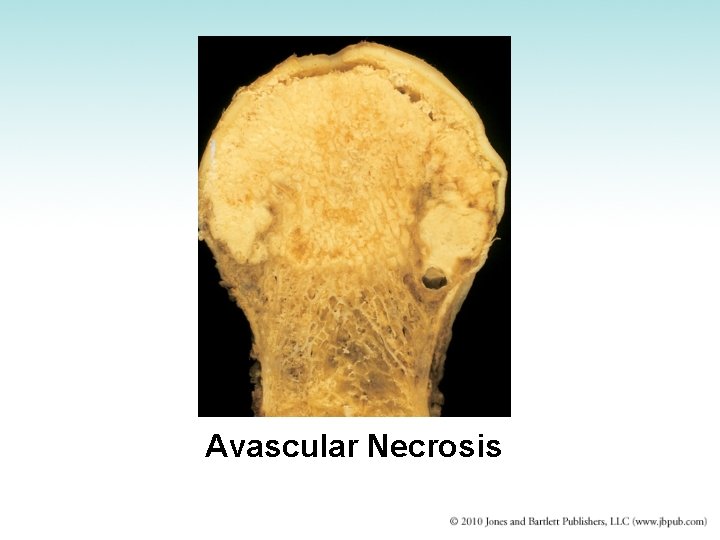

Avascular Necrosis • Interference in blood supply to the epiphysis of bones • Results in necrosis and degeneration at ends of bone • Disturbance in blood supply probably from injury • Local pain and disability • Common sites – Femoral head, tibial tubercle, articular surface of femoral condyle

Avascular Necrosis